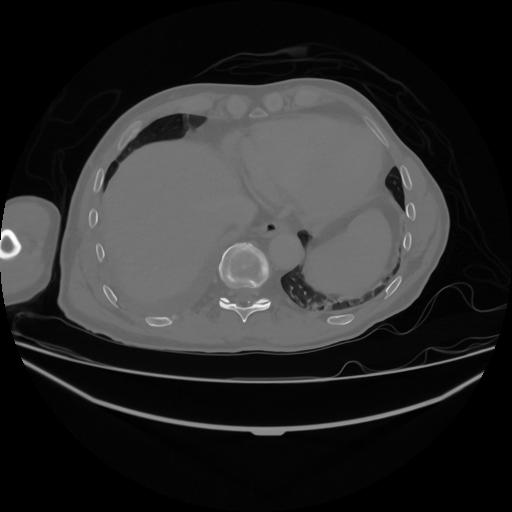

5 CUERPO,CE,Vol,1.0,CUERPO,,